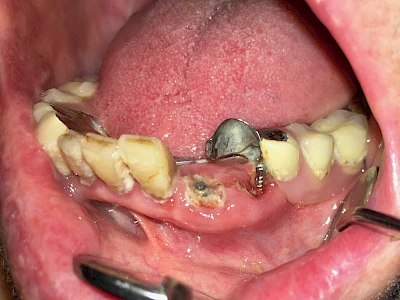

Bricht ein Zahn oder eine künstliche Zahnkrone ab, kann in der Tiefe des Zahnes Fremdmaterial zum Vorschein kommen. Wurzelkanalfüllungsmaterialien können wie "Fleischfasern" zwischen den Zähnen irritieren und sollten deshalb entfernt werden. Harte Wurzelkanal-Stifte können scharfkantig sein und die umliegenden Weichteile verletzen.